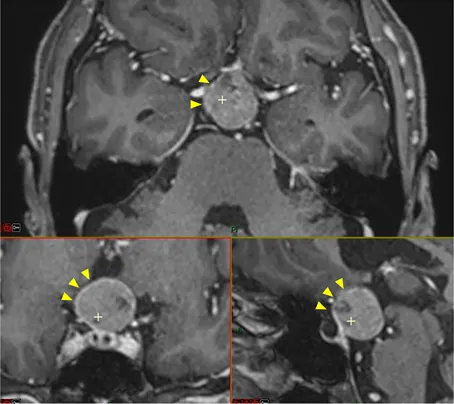

具体分析:MRI显示一个球形病变占据垂体漏斗后部及鞍上间隙,且肿瘤与垂体柄和正常垂体组织紧密相邻(黄色箭头)。

视交叉(绿色箭头)和动眼神经(蓝色箭头)由于受到肿瘤挤压而产生移位,视交叉已经变薄。此外,肿瘤与颈动脉(白色星号)、后交通动脉(红色箭头)、大脑前动脉(白色星号)和大脑后动脉(黄色箭头)紧密粘连,术中剥离困难,存在较大的出血风险。

要求:手术必须要在保留垂体及其功能的基础上进行安全切除,同时不损伤周围重要神经血管,谨慎将肿瘤与其剥离开来。